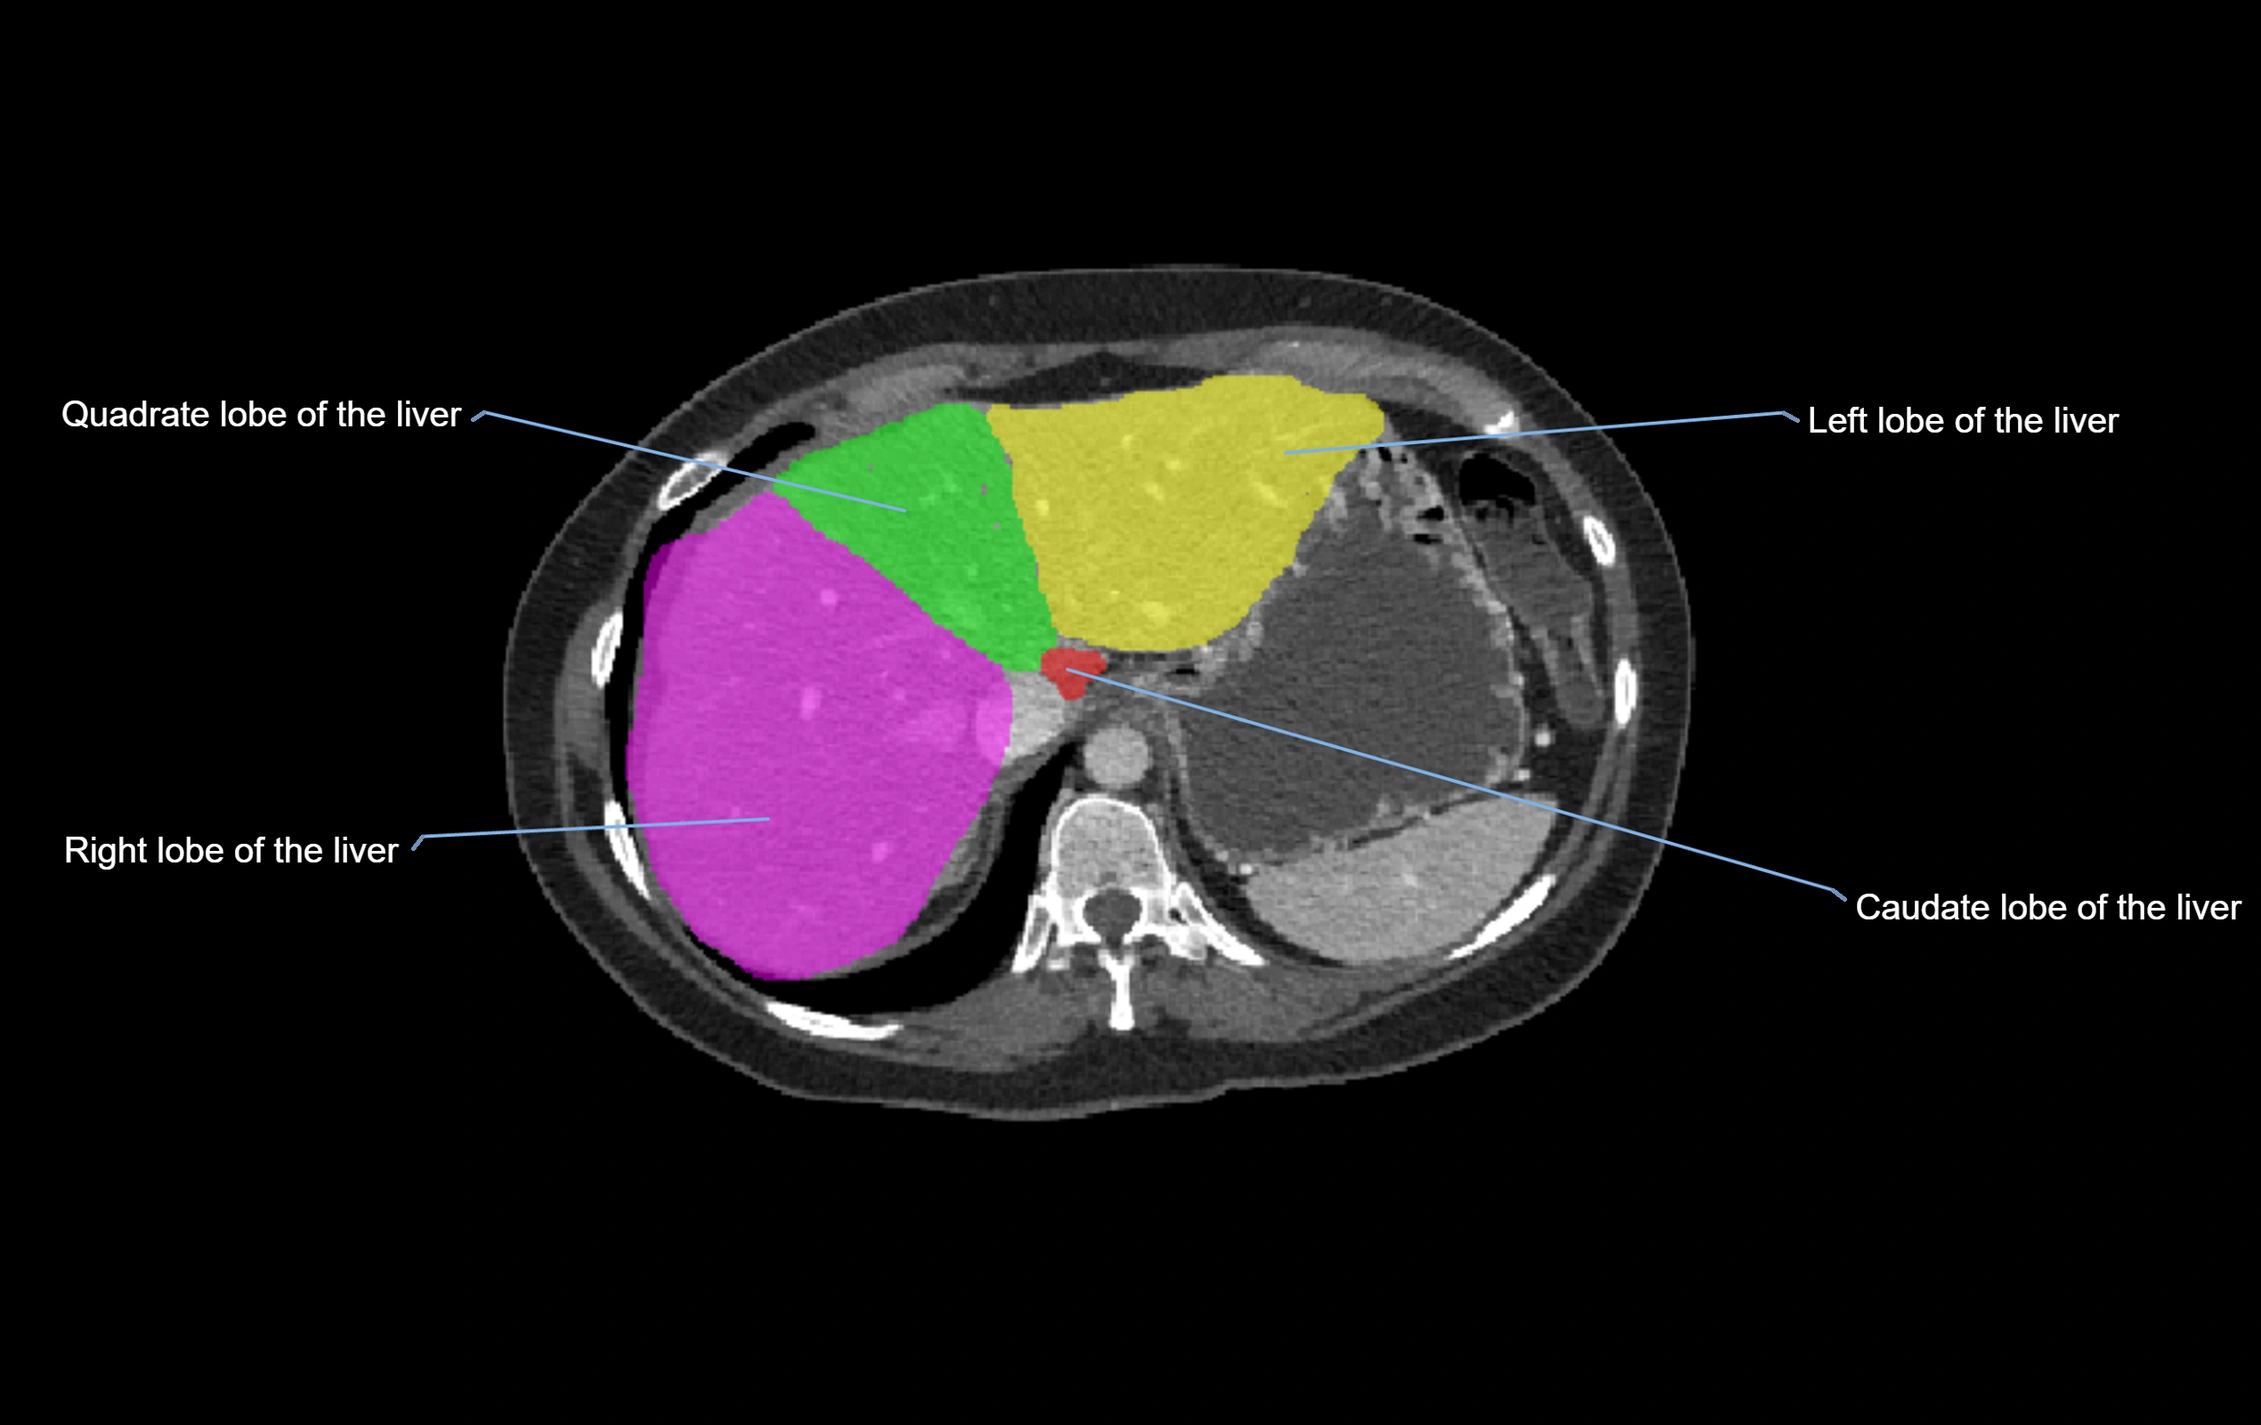

CT Image

image